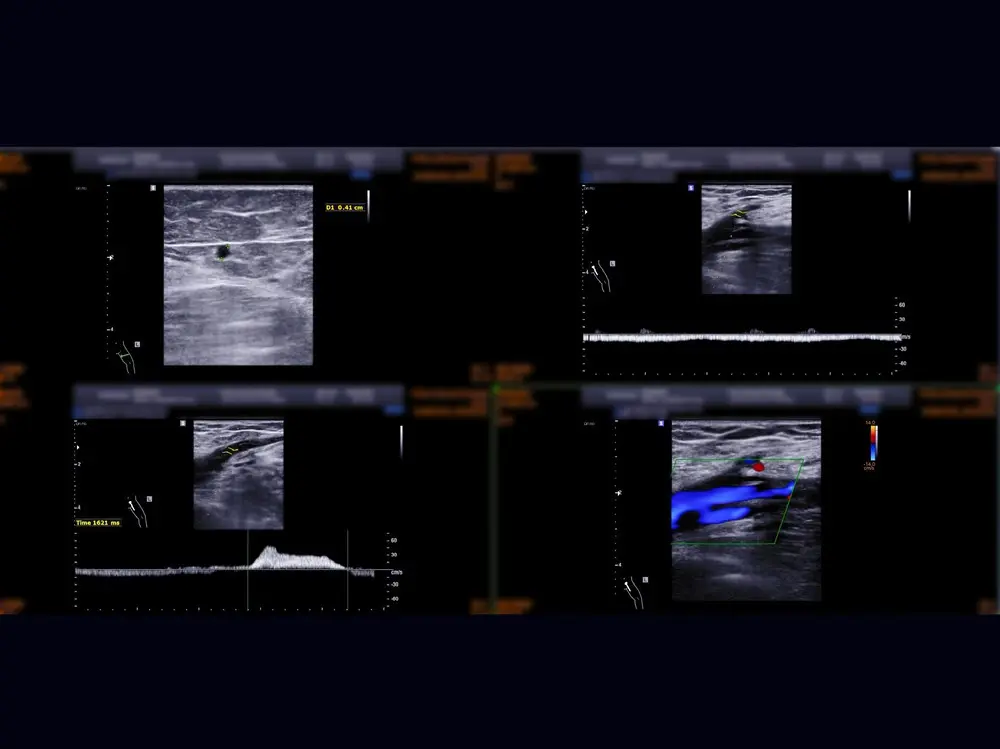

A Deep Vein Thrombosis scan is a non-invasive medical diagnostic imaging to check the presence of thrombus (blood clots) and blood flow in the large veins in the arms or legs. This scan also looks at superficial veins in the arms or legs if there are any blockage due to blood clots. However, the occurrence of blood clots is more common in the legs. This scan includes the assessment of femoral veins, sapheno-femoral junction, popliteal veins, sapheno-popliteal junction, and calf veins in your legs. It can help your healthcare professional to determine an immediate treatment in various conditions in your peripheral veins.

The blood clots can be a medical emergency as they can reach into the lungs and can cause pulmonary embolism which can be life threating.

The most common conditions of the deep veins in the arms or legs can be thrombus in deep vein.

Thrombophlebitis.